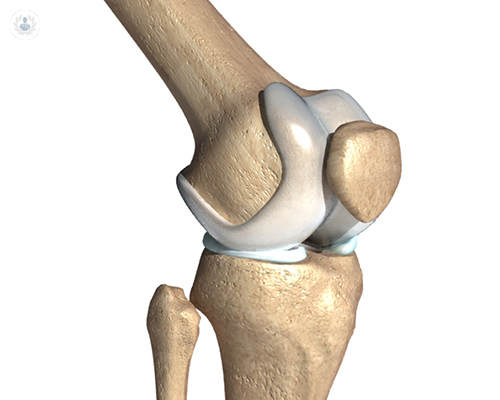

• articulacion-rodilla

Redacción de Top Doctors

20/11/2017

Prótesis de rodilla para la artritis y artrosis avanzadas

La posibilidad de introducir una prótesis articular es una revolución en Traumatología y Cirugía Ortopédica, ya que permite a miles de personas recuperar la movilidad y mejorar su calidad de vida. Hablamos con el Dr. lafuente Cuenca sobre la operación para colocarlas.